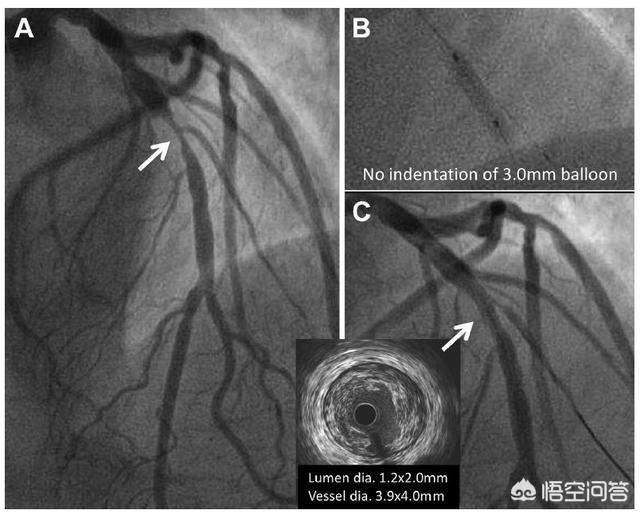

Mais il s'agit là d'un jugement subjectif. Existe-t-il un test objectif capable de fournir une analyse qualitative ? La réponse est oui : la FFR, ou fraction de réserve de flux, est un test plus objectif. Ce test peut mesurer si le vaisseau sténosé est ischémique ou non, plutôt que de se fier à la seule expérience de l'interventionniste ; une FFR > 80 % signifie qu'il n'y a pas d'ischémie myocardique et que la pose d'un stent n'est pas nécessaire ; une FFR < 75 % signifie qu'il y a une ischémie myocardique et que la pose d'un stent est nécessaire.

La pose ou non d'un stent doit donc être combinée aux symptômes cliniques et à la coronarographie. Si l'on n'est toujours pas sûr que la lésion soit ischémique ou non, il est recommandé de procéder à un examen FFR afin d'obtenir des preuves plus objectives.